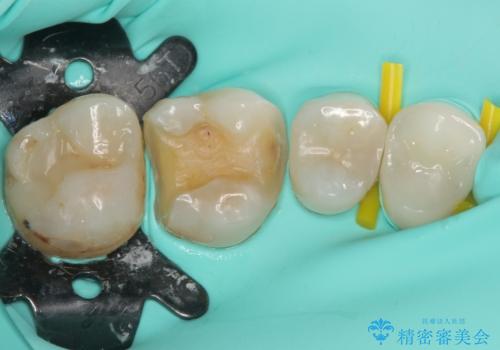

- 奥歯の詰め物や周辺の歯が欠けてしまったとのことで来院された患者様です。

上顎は、元々の詰め物が小さく、欠けた範囲も大きくなかったため、セラミックインレーにて修復治療を行うこととしました。

一方下顎は、元々のむし歯の範囲が広かったため、長期的な予後を踏まえ、セラミッククラウンにて補綴治療を行うこととしました。